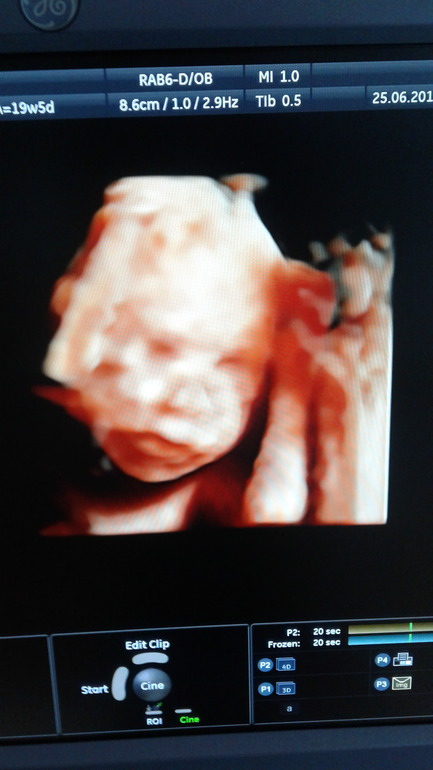

Узи делала в 19,5 недель. Малыш 370 грамм. Соответствует сроку. Дома рассмотрела фотографию, губы папины)))))😄

Но в почти 20 недель мальчишку нам подтвердили, ничего не отпало, писюн и мошонка на месте 😅😙